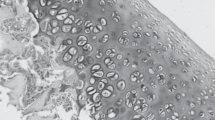

The biochemical and molecular analysis of rat cartilage tissue with monosodium iodoacetateinduced osteoarthritis established the increase in the expression levels of Ptgs2 and Tgfb1 genes and the increase in ROS production compared to the corresponding control group of animals. This indicates the activation of inflammatory and destructive processes, impairment of the cellular redox balance, and the development of oxidative stress in the tissues. When using a chondroitin sulfate preparation under the same conditions, the expression levels of these genes, as well as the content of the superoxide anion radical and organic hydroperoxides, were closer to control values compared with experimental osteoarthritis, indicating the antiinflammatory and antioxidant properties of the drug used and its efficiency in osteoarthritis treatment.